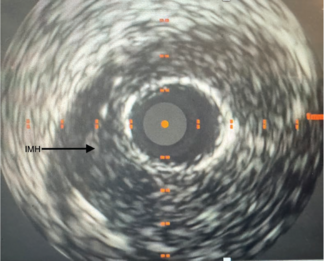

Spontaneous or trauma-related coronary intramural hematoma, a subset of coronary artery dissection, is a rare, challenging, and under-recognized diagnosis constituting 1% to 4% of all myocardial infarctions.(1)

Case Report A 45-year-old woman, who was a nonsmoker with a known case of hypertension, presented with a history of pain in her right upper limb on exertion for the past 6 months. There was no history of any neurological symptoms, trauma,...